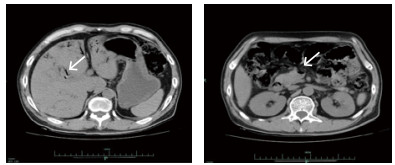

患者,男性,45岁,有长期在老挝居住史,1个月前回本地。因"纳差乏力5 d,少尿伴反应迟钝1 d"入院。否认糖尿病、高血压、腹部外伤及手术病史。有吸食毒品史数年,自行戒毒1个月余。1个月前有牙齿修补术病史,术后曾出现一过性胸闷及乏力感,当时未就诊治疗。5 d前无明确诱因下出现明显纳差乏力,1 d前在外院就诊,查血肌酐正常,未测血糖。近1 d来症状加重,伴尿量减少,反应迟钝,夜间急诊来台州市中心医院就诊。入院查体:体温37.2℃,心率147次/min,呼吸37次/min,血压88/60 mmHg(1 mmHg=0.133 kPa),氧饱和度100%。神志不清,双侧瞳孔直径0.25 cm,对光反射存在,心律齐,未闻及明显杂音,呼吸音清,未闻及啰音,腹平软,无明显压痛及反跳痛,双下肢无水肿,肢端皮温低,四肢存在自主活动,巴氏征阴性。辅助检查:白细胞计数10.5×109/L,中性粒细胞90.7%,血小板计数280×109/L,超敏C反应蛋白134.00 mg/L;血钠157 mmol/L,白蛋白28.4 g/L,淀粉酶290 U/L,全血葡萄糖76.14 mmol/L,血酮体7.6 mmol/L。血清肌酐443 μmol/L,尿素氮26.3 mmol/L;降钙素原33.74 ng/ml;血气分析:氧饱和度96.3%,血乳酸5.5 mmol/L,pH 7.150,PCO2 12.2 mmHg,PO2 111.0 mmHg,实际碳酸氢根4.1 mmol/L,实际剩余碱-24.9 mmol/L。全腹部CT示,肠系膜上静脉及门静脉远端属支多发积气,肠道水肿不明显(图 1)。入院诊断:休克:感染性休克?、糖尿病高渗性昏迷、糖尿病酮症酸中毒、急性肾功能不全、血流感染?

| 图 1 入院时CT检查结果 |